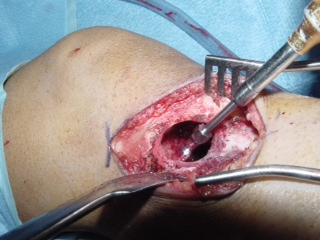

Fig. 4

Fig. 5

Fig. 6

Fig. 7

Fig. 4-7: MR imaging of a benign fibrous histiocytoma of the proximal tibia demonstrates a heterogeneous high signal intensity and low signal intensity with surrounding sclerotic bone on T2-weighted images. T1-weighted images show low signal intensity. No soft tissue mass is visible.